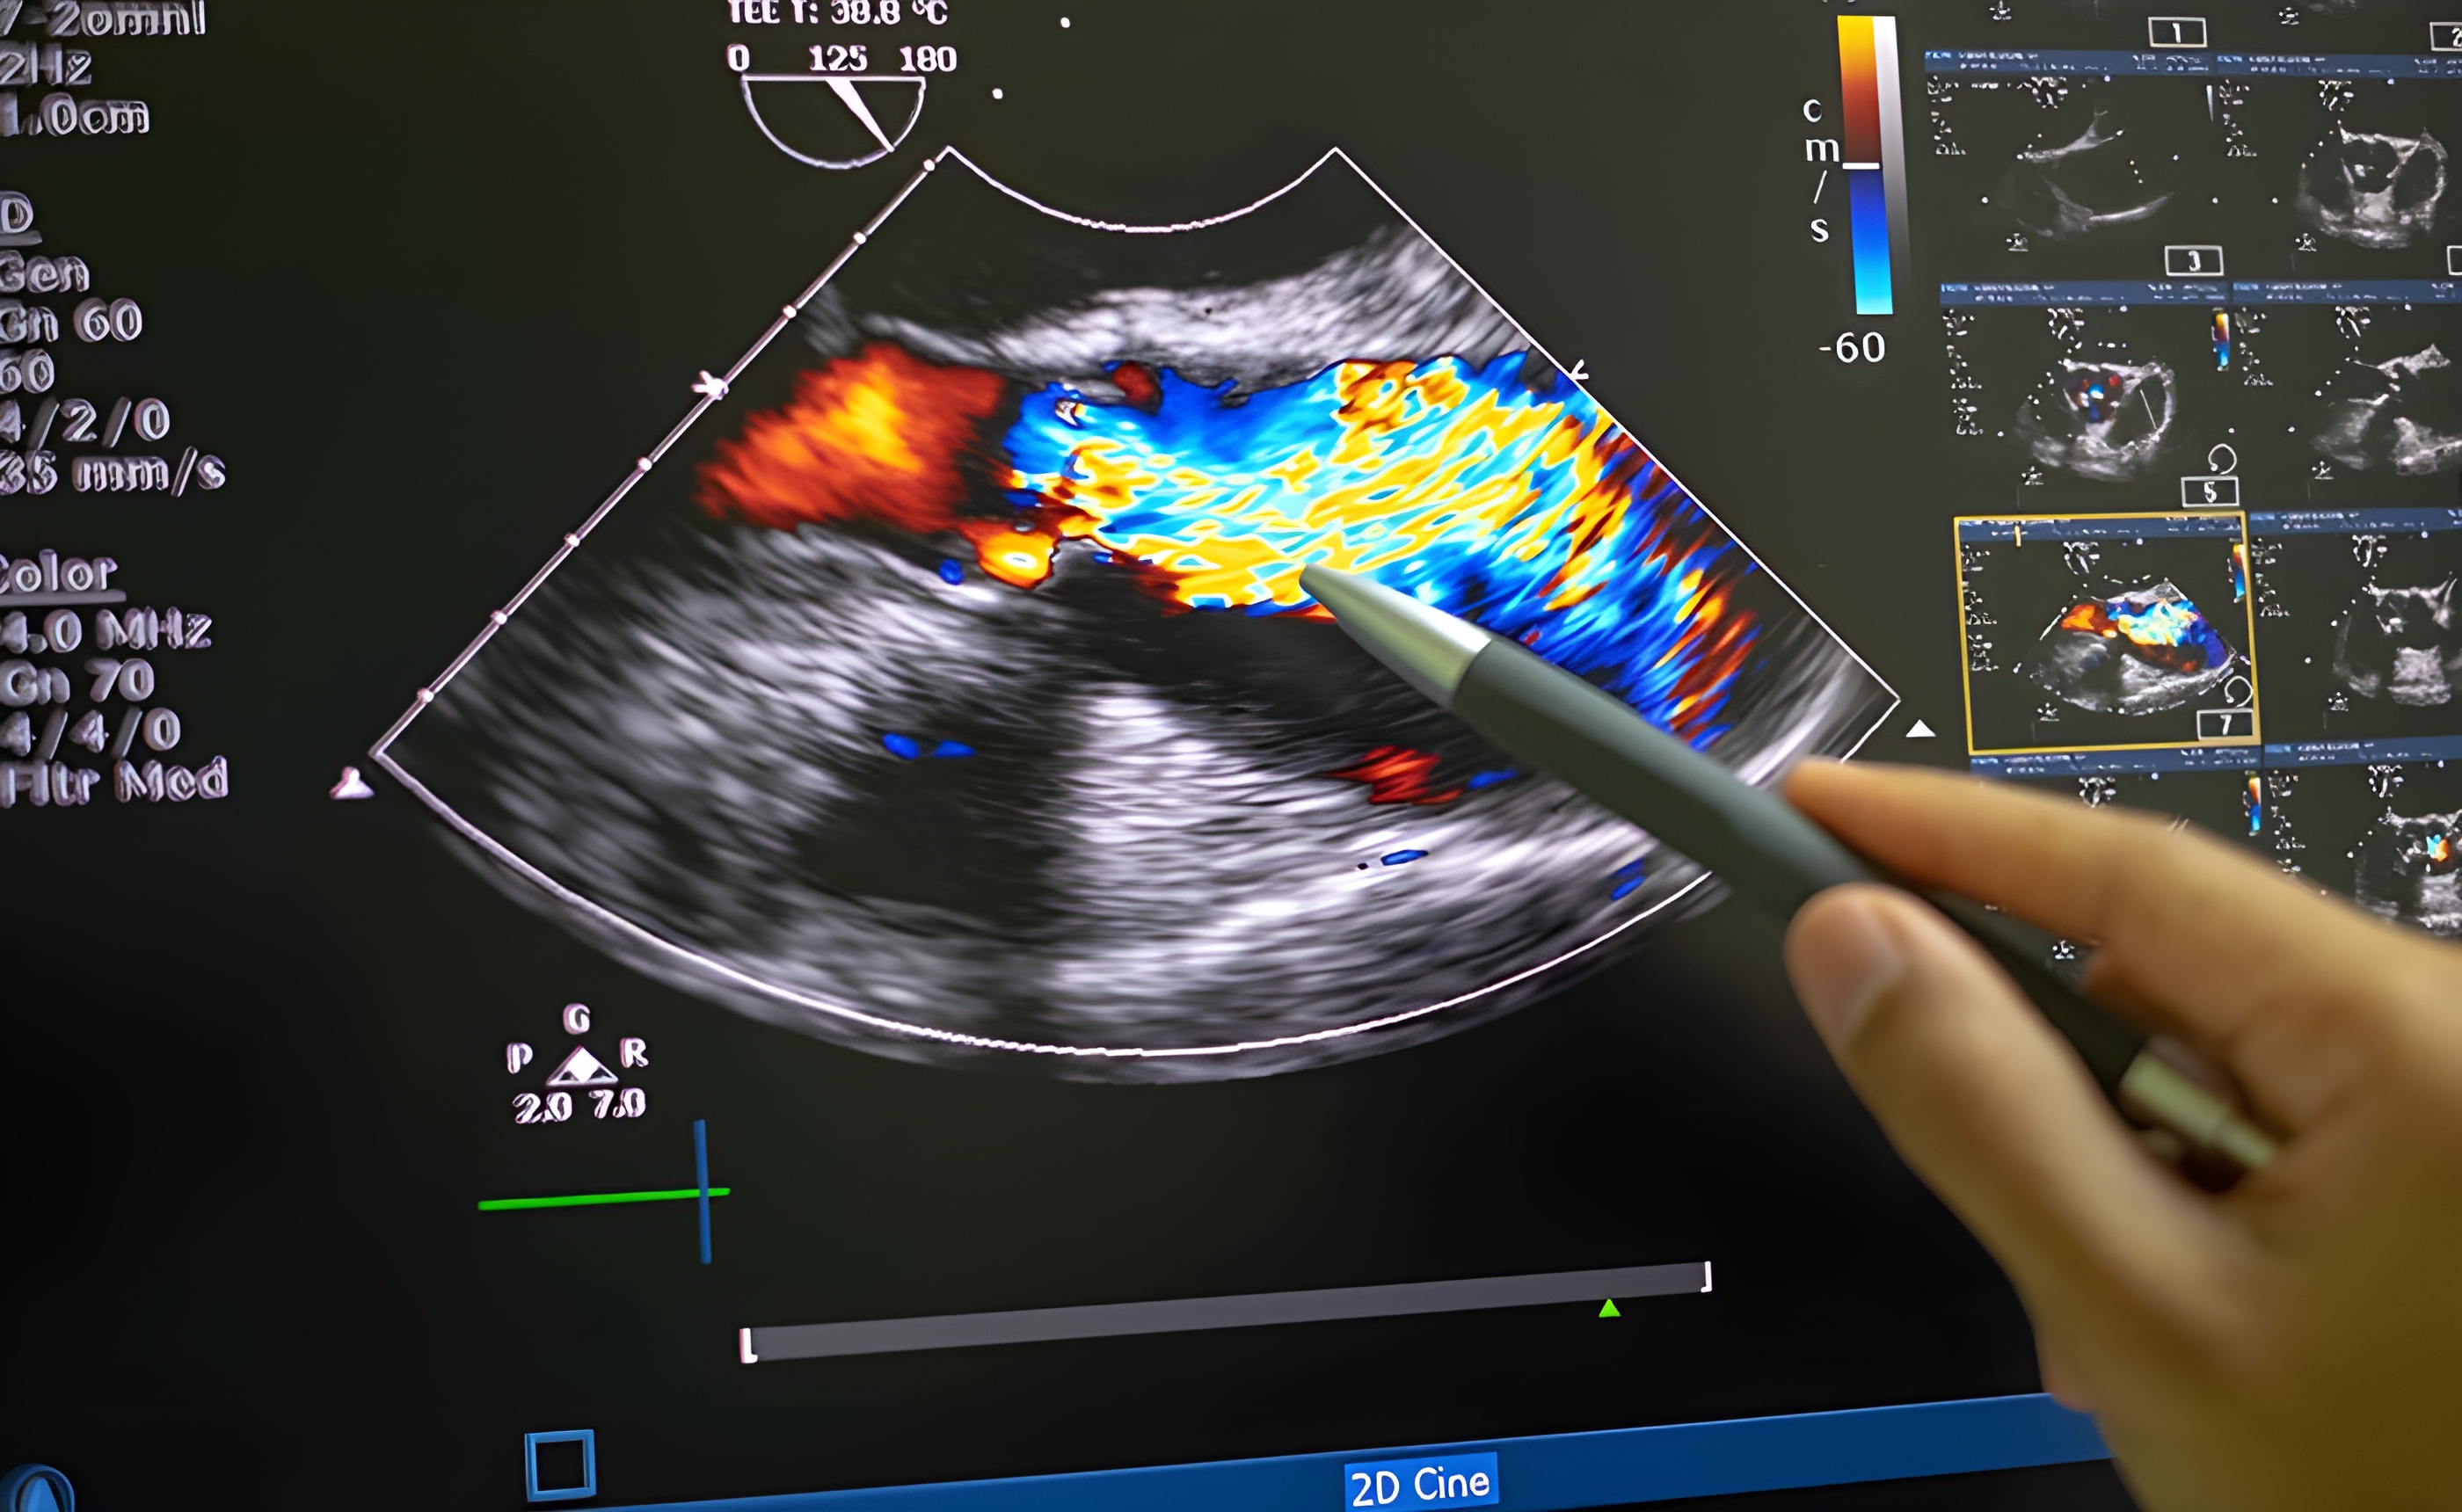

Permite visualizar en tiempo real el flujo de sangre a través de arterias y venas. El ultrasonido doppler puede ser arterial, venoso o carotídeo

Ejemplo de Imagen informativa